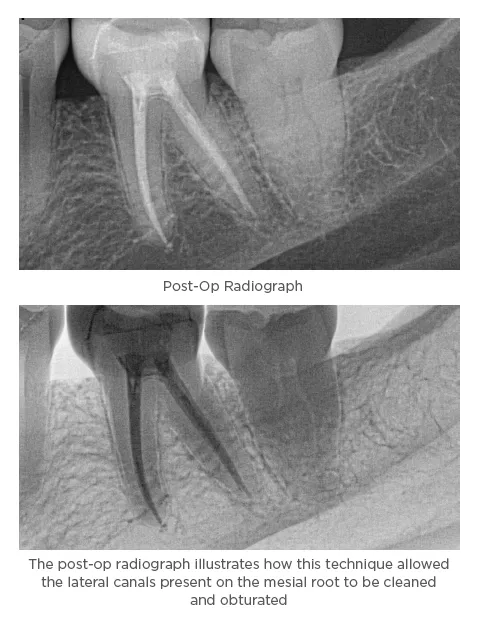

Obturation

After verifying the fit of the matching sized gutta percha into the canals, I coated them in Tubli-Seal™ Xpress (Kerr) canal sealer using the auto mix tip and re-inserted them into their respective canals. I then used the elements™ IC unit to sear off the excess gutta percha at the canal orifices and performed a single motion downpack with the heated plugger to approximately 3-5mm from the apex. Then, using the obturator cartridge tip, I applied additional Tubli-Seal™ Xpress into the canals and backfilled using a continuous wave obturation technique and compressed and condensed the gutta percha with Buchanan Hand pluggers. The elements™ IC system allows me to obturate complex cases with a three-dimensional volumetric fill and not have to rely on sealer alone to fill in the voids and lateral canals. It provides excellent visibility into the canals so that my view is not obstructed, and the tips are flexible so that they can follow the natural curvature of the canals and reach difficult to access areas. It is ergonomic, and easy to use, and the disposable cartridge system eliminates the need to use pellets that can be messy or carrier-based obturators that come with their own set of problems. The elements™ IC has improved upon the many great attributes of its predecessors and consistently provides excellent results.